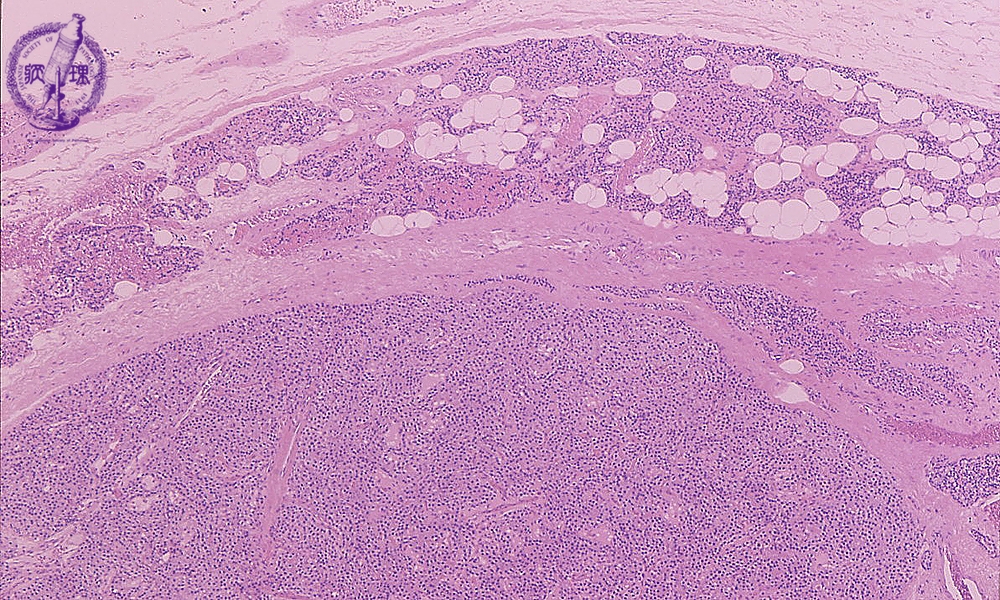

- (2)Parathyroid adenoma (MEN)

Microscopic findings (HE stain, low power view). Parathyroid adenoma. A fibrous capsule was detected around the tumor (deliminated with a dotted line). Stromal adipose cells are absent in the tumor, while non-neoplastic parathyroid tissue (arrow) contained adipose tissue components.